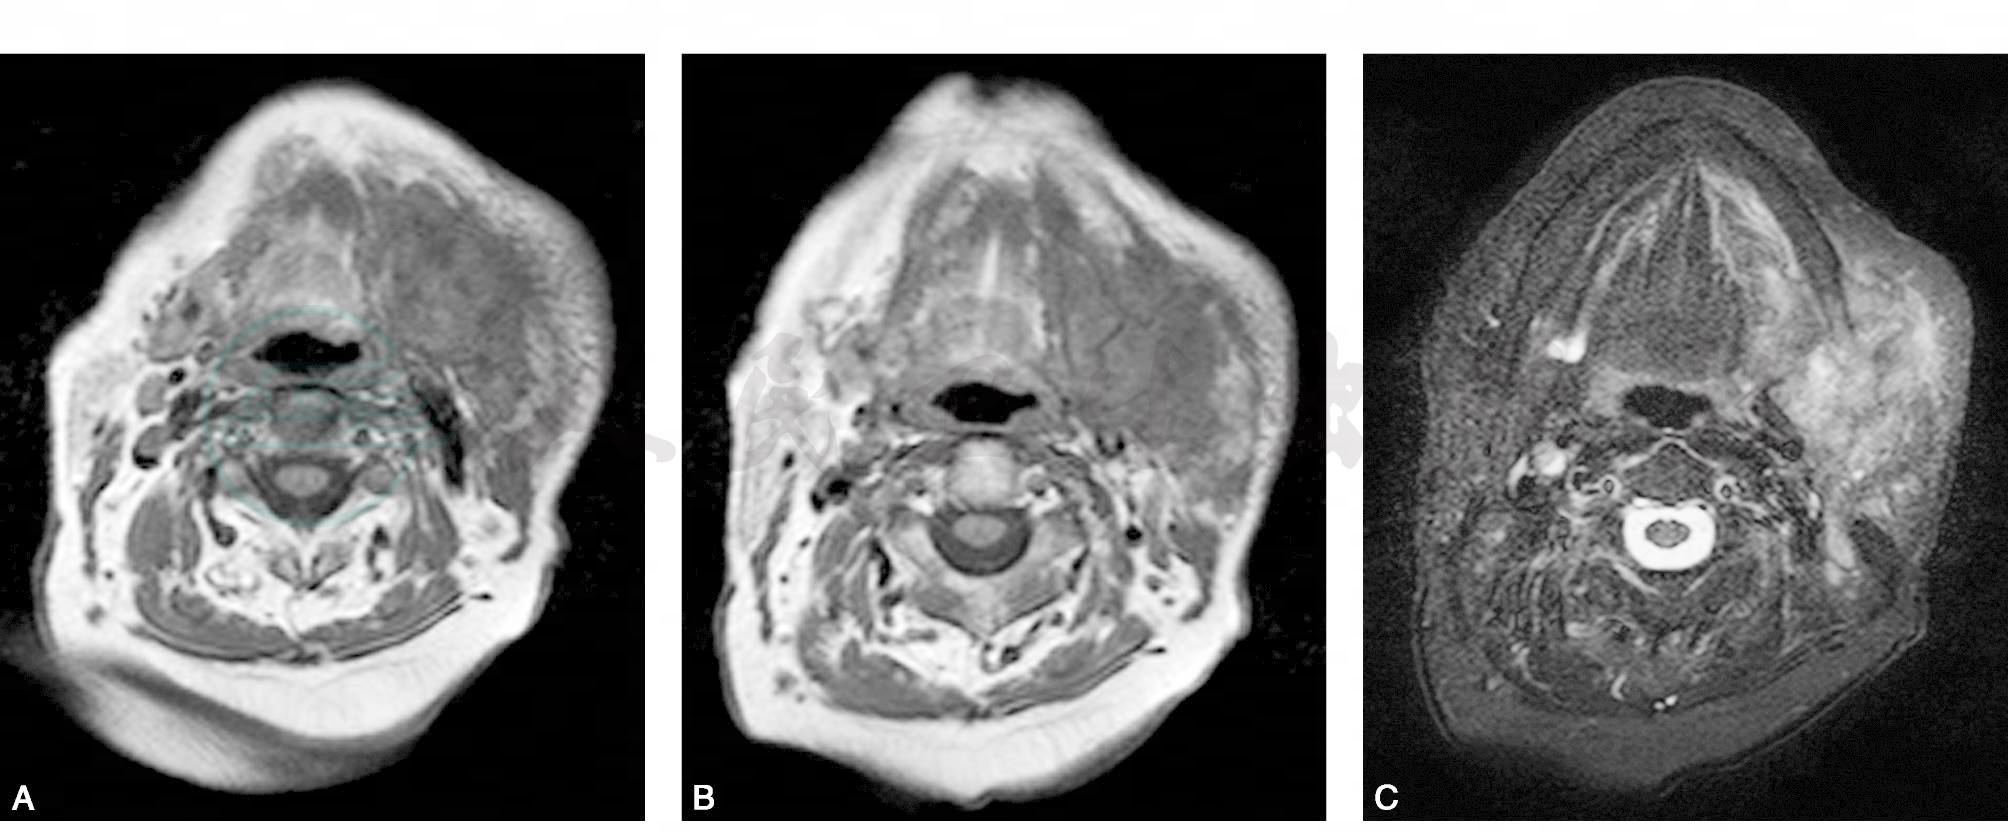

肿瘤位于左侧颌下区,左侧下颌骨骨质破坏,周围见软组织肿块,T1WI上呈不均匀稍低信号,T2WI压脂上呈不均匀稍高信号,边界欠清;增强扫描不均匀明显强化,可见多处无强化坏死区。约为4.4cm×5.7cm,与颌部皮下脂肪及下颌部内侧肌间隙、脂肪间隙等分界不清。左侧颌下腺局部受侵,信号不均匀。右侧腮腺未见异常信号。双侧颈部、下颌部、颏下可见多个淋巴结影,最大一个位于左侧颈根部皮下直径约为1.5cm左右(图1)。

图1 颌下区黏液表皮样癌

A~B. T1WI横断位;C~D. T2WI压脂横断位;E~F. T1WI压脂增强横断位;G. HE×100